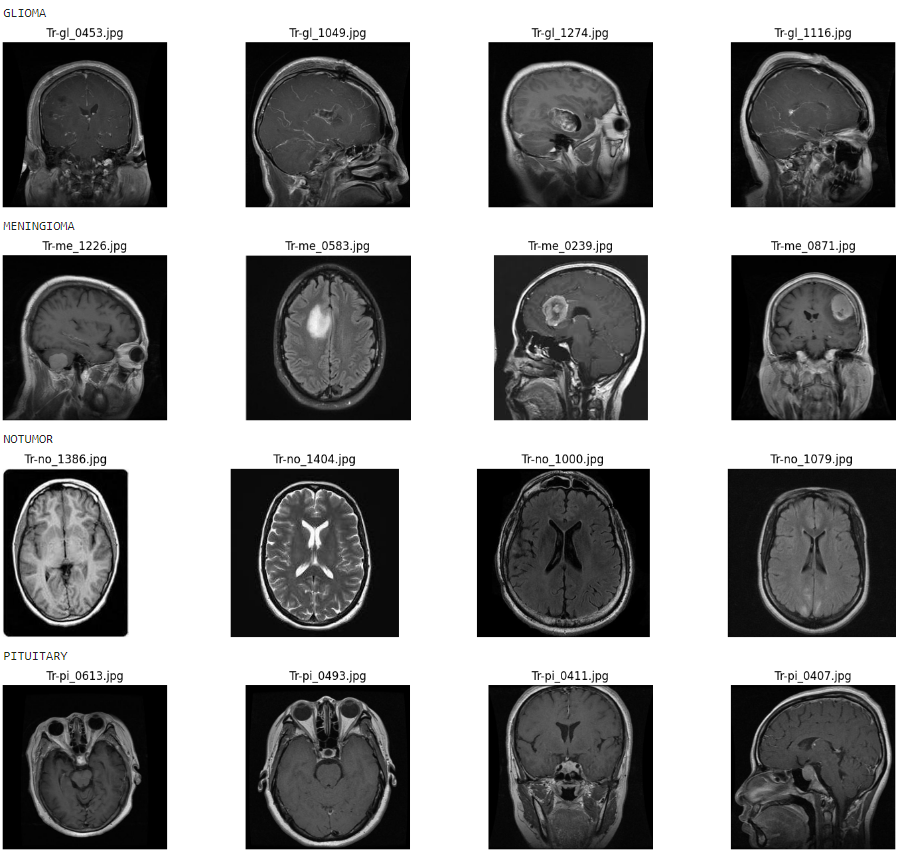

Fine-tuned ResNet-50 CNN in PyTorch that classifies brain MRI images into four categories: Glioma, Meningioma, No Tumor, and Pituitary. Evaluated via confusion matrix to identify challenging tumor types and assist earlier, more accurate diagnoses.